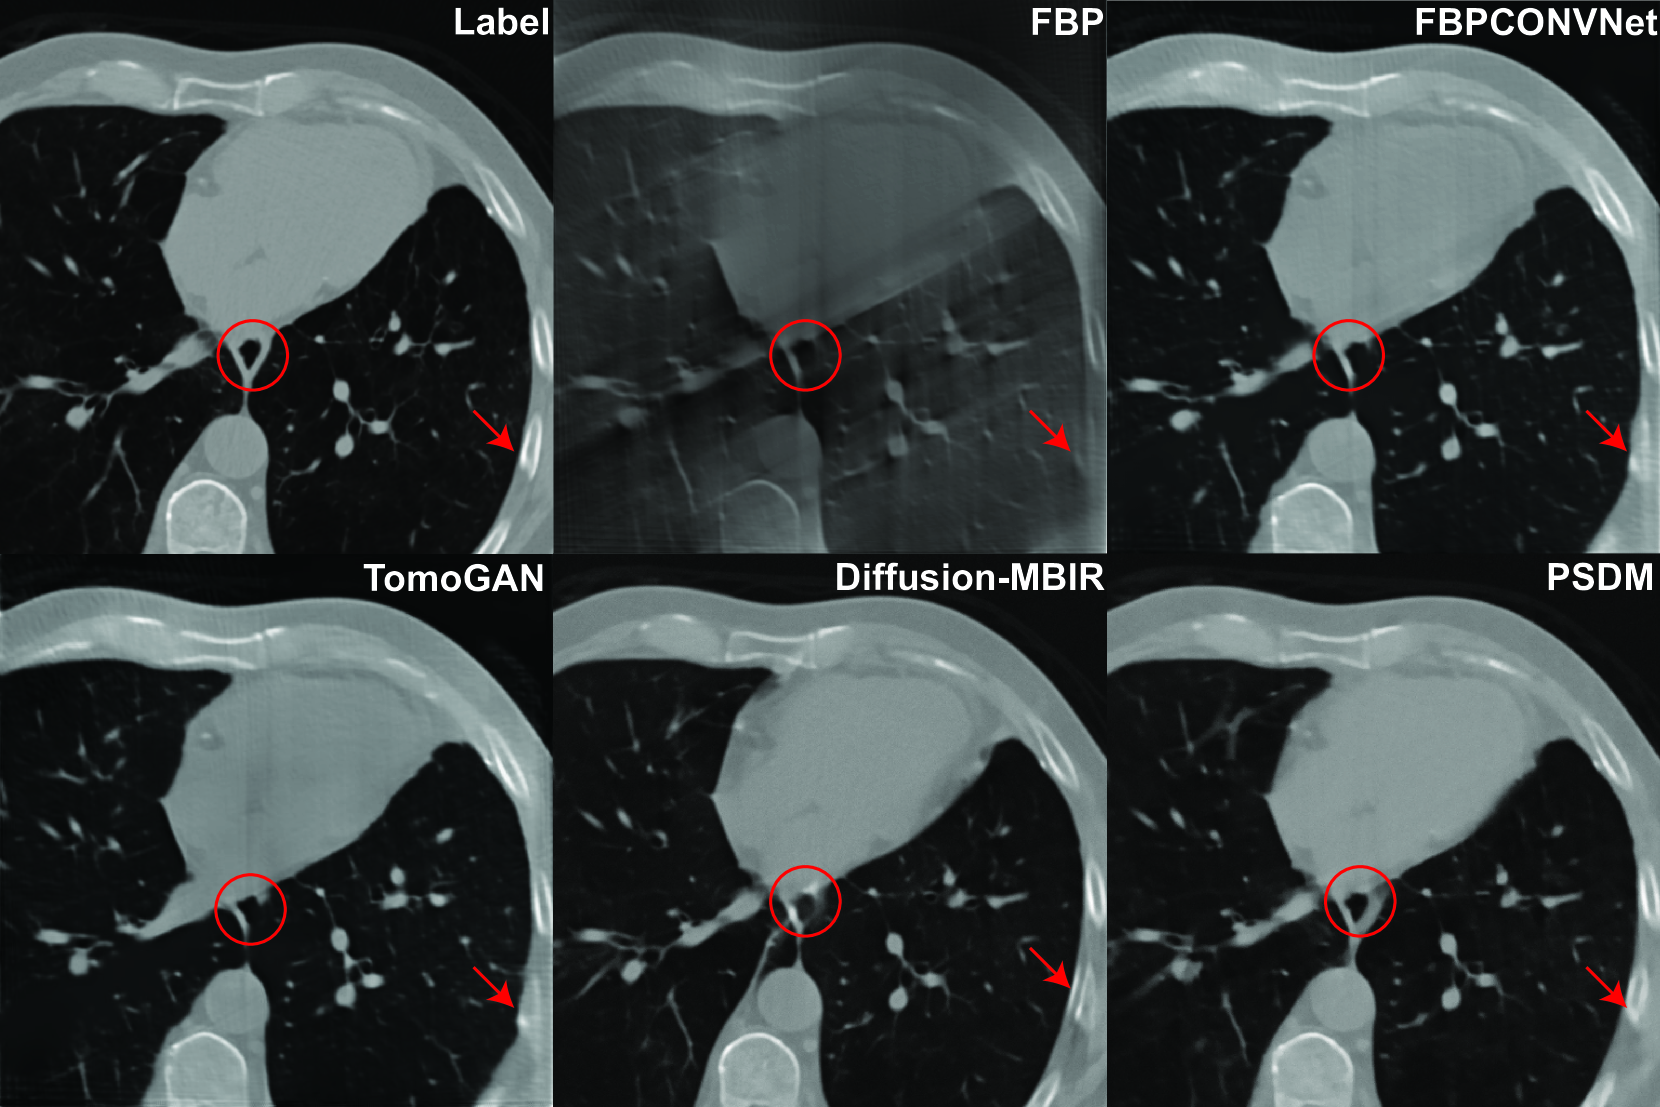

Refer to caption

Figure 5: Reconstruction results from the AIMI COCA dataset with 120 views using different methods. The display window is [900900-900- 900 1000100010001000] HU.

4.2.1 Stanford AIMI COCA results

To advance our clinical dataset evaluation, the Stanford AIMI COCA dataset[42] is employed. The COCA dataset is a compilation of 789 gated CT scans, with each scan corresponding to an individual patient. On average, every patient contributes roughly 50 image slices, and each image slice possesses a resolution of 512 x 512 pixels. The NCSNPP model is trained with data from 60 patients, totaling approximately 3,400 image slices. Apart from the image size, all other parameters remain consistent with the simulation training. The reconstruction results from 120 views appear in Fig. 5. Significantly, our proposed method produces images of enhanced quality characterized by prominent features and sharp image boundaries. This is especially discernible in the areas and structures underscored by red circles and arrows. In contrast, other algorithms tend to obscure certain details and introduce blurring.